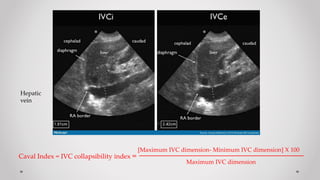

- Siêu âm đã được chứng minh có thể đo kích thước tĩnh mạch Chủ dưới (IVC) và thay đổi kích thước IVC

với hô hấp một cách không xâm lấn, mà sự thay đổi kích thước IVC này có tương quan đến áp suất tâm

nhĩ (P) và tình trạng huyết động học

- Cách thực hiện:

• Đo đường kính IVC  2 phương pháp:

1. Đo cách bờ nhĩ (P) # 2-3cm theo mặt cắt dọc trong một chu kỳ hô hấp

2. Đo cách Tĩnh mạch gan # 1-2cm theo mặt cắt dọc trong một chu kỳ hô hấp

• Tính “Caval index” dựa vào giảm tương đối đường kính của IVC từ thì thở ra đến thì hít vào

- Lưu ý rằng, kích thước IVC trên BN thở máy ít đáng tin cậy hơn bởi những khác biệt của áp lực lồng ngực

khi được thông khí áp lực dương so với áp lực âm thông khí bình thường  do đó:

 Bệnh nhân thở tự nhiên (Spontaneously breathing patients): Đường kính IVC và sự

thay đổi đường kính khi hô hấp phản ánh áp suất tâm nhĩ (P)

 Bệnh nhân thở máy (Patients with mechanical ventilation): Thay đổi đường kính của IVC giúp tiên

lượng đáp ứng với việc bù dịch

1. Đánh giá TM chủ dưới (IVC)

Caval Index = IVC collapsibility index =

[Maximum IVC dimension- Minimum IVC dimension] X 100

Maximum IVC dimension

Hepatic

vein